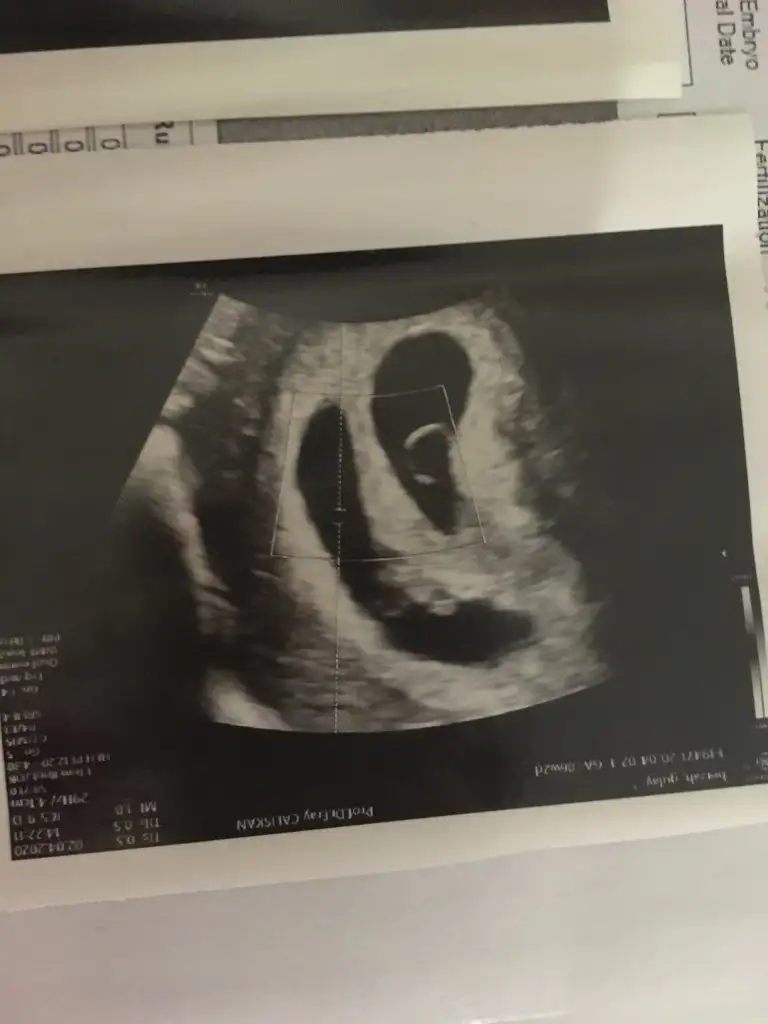

Evet benimde ikiz . Benimkilerde böyle

Sizinde biri daha küçük sanırım çekim boyutundan değilse keseler daha büyük kaç haftalık şuan sizin biri erkek biri kız gibi doğuyo içime bnm biri yuvarlak biri uzun diye tabi allah bilir sağlıkla doğsunlarda ikiz gebelk daha zorlu allah bize ve diğer tüm gebelere kolaylık versin

Amin inşallah .ben bugün tam 8+0 oldum.evet benimde biri küçük. Küçük olanın kalp sesini duymadık henüz. 2 hafta önce gitmiştik. Yarınn tekrar gideceğiz. Çok merak ediyorum